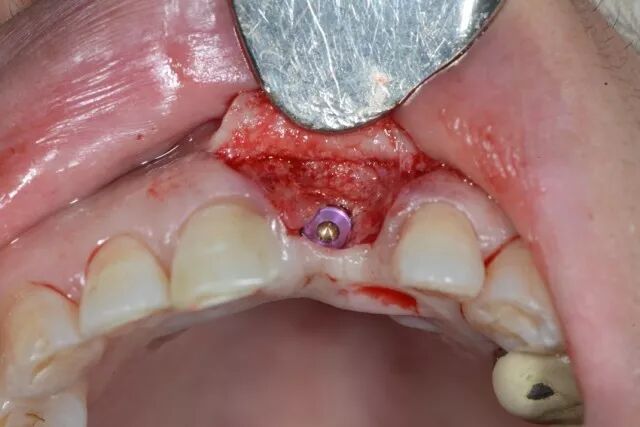

骨修復(fù)型手術(shù)實例一

外傷拔牙后三個月

植骨

覆蓋吉特瑞

種植及成骨效果